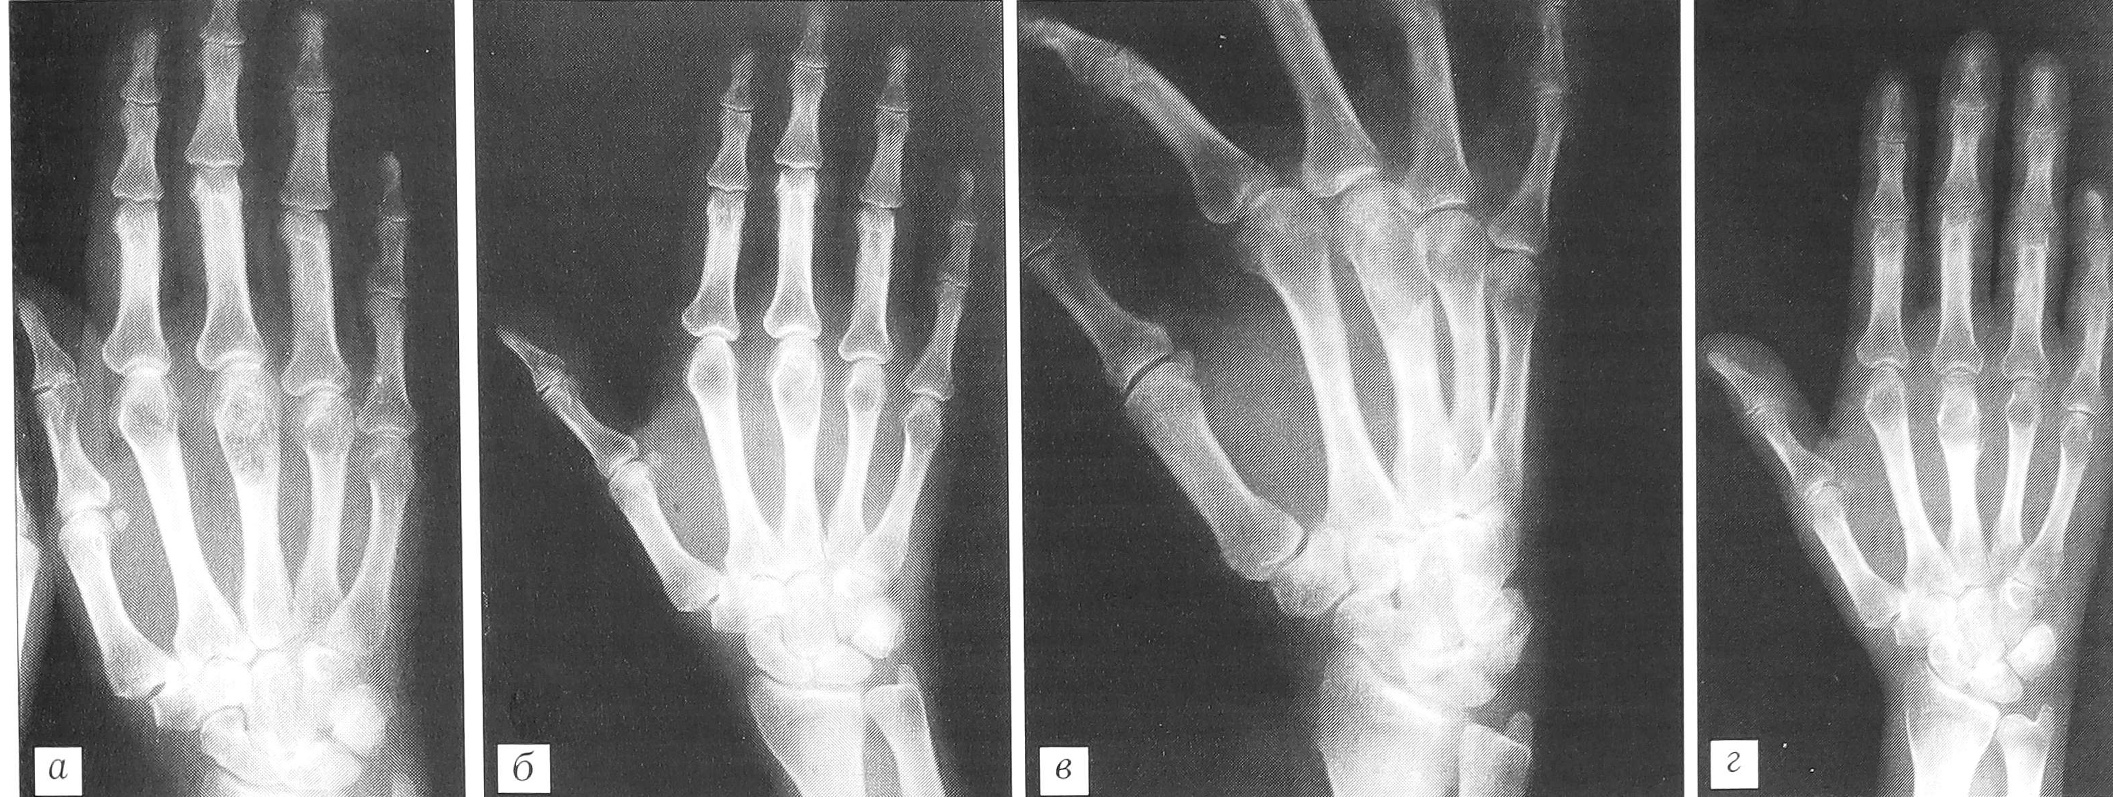

Клинический пример. Больная К., 51 года, поступила в отделение костной патологии ЦИТО 21.05.01 с жалобами на боли в области III пястно-фалангового сустава правой кисти, усиливающиеся при физической нагрузке. При клинико-рентгенологическом обследовании выявлен очаг патологической деструкции в головке III пястной кости (рис. 5, а). Диагноз: хондрома III пястной кости. 22.05.01 произведена операция: краевая резекция III пястной кости, удаление патологической ткани с последующей электрокоагуляцией стенок полости и пластикой дефекта «Остеоматриксом» (рис. 5, б). Послеоперационное течение без осложнений. Рентгенологическая картина через 1 и 5 мес после операции свидетельствует о постепенной биодеградации пластического материала и замещении его собственной костной тканью (рис. 5, в, г).

Рис. 5. Рентгенограммы больной К. 51 года. Диагноз: хондрома III пястной кости.а — до операции; б — после операции с пластикой дефекта «Остеоматриксом»; в — через 1 мес; г — через 5 мес.